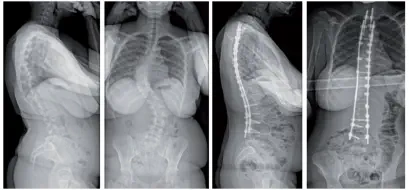

14 Jahre, adoleszente idiopathische Skoliose mit doppelter starker Krümmung, T2/L4 Arthrodese mit Jazz Frame-Fixation.